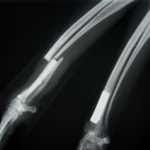

症例3:キルシュナーワイヤーのピンニングによる整復

ペルシャ猫 11ヶ月齢 雄

他院にて左大腿骨遠位の成長板骨折(salter-harrisⅠ型)が認められており、治療相談を目的として来院。当院にて、キルシュナーワイヤーを用いたピンニングにより骨折部位の整復を行いました。術後の経過は良好で、現在も経過観察中です。

術前レントゲン

術後レントゲン